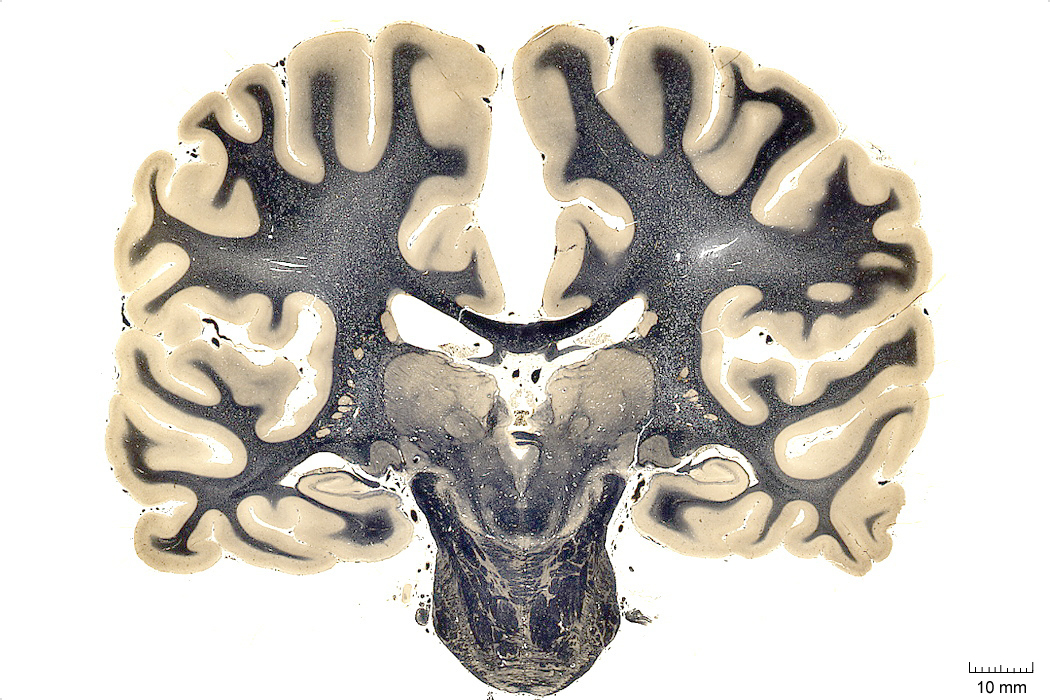

Note:

- white matter: so named because of the bright shiny appearance to the naked eye

- gray matter: so named because it is less bright, a little more dull looking. But nothing dull about it.

- Cell stain is Nissl stain

- Fiber stain is Luxol Fast blue

- Luxol fast blue stain

- stain and observe myelin for light microscopy

- a copper phthalocyanine dye

- soluble in alcohol

- binds bases found in lipoproteins of myelin sheath

- Nissl stain

- basic dyes (e.g. aniline, thionine, or cresyl violet)

- stain negatively charged RNA blue

- Nissl substance (rough endoplasmic reticulum)

Cell groupings: cortex vs nuclei

Note:

Here is one of those cell body violet stained sections-- you can see the cortical sheet and different subcortical nuclei in the thalamus, etc. We will go over this in more detail later.

Cerebellum

Note:

Cerebellum is latin for ‘little brain’, and it does have a striking organization with lobes and fissures similar to the folding of the cerebral cortex to increase surface area and packing density of neuronal interconnections. You can see here its main cell body layer, obvious in this purple nissl stain for cell bodies here. It’s in this layer where you will find the beautiful purkinje neurons that we saw images of in lecture 01.